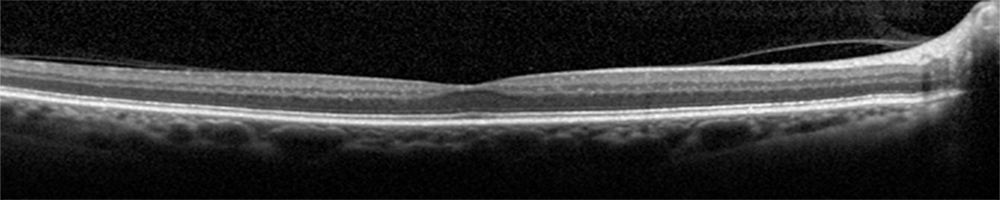

Retinal diseases, such as age-related macular degeneration (AMD) or diabetic retinopathy (DR), are the major cause of blindness in a large percentage of world population. These pathologies, currently affect over 8.7% of the world population and 159 million people worldwide, respectively. Retinal optical coherence tomography (OCT) imaging has become an indispensable diagnostic tool in Ophthalmology to early detect, treat and monitor these diseases. Automated retinal image analysis has the potential to improve the diagnostic process and make treatment monitoring more effective.

However, efficient leveraging key information for diagnosis is a complex task, since the retinal OCT images are corrupted by speckle noise, distorted with respect to the anatomy and the patient movement in the acquisition process, and of a wide range of varying image intensity. So, many traditional automated solutions and techniques do not suffice to accurately extract the required discriminative information.

The goal of this challenge is to call different automated algorithms that are able to detect DR disease from normal retina on a common dataset of OCT volumes, acquired with Topcon SD-OCT devices. We made available a dataset of OCT volumes containing Normal and DR cases with accompanying reference annotations. We invite the medical imaging community to participate by developing and testing existing and novel automated retinal OCT image classification methods.